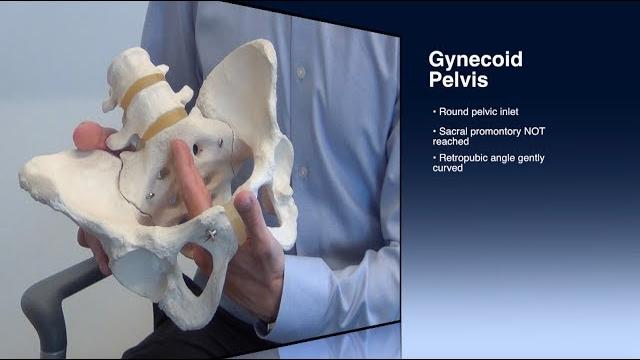

Для вашего запроса найдены видео: Guided meditation for pelvic floor relaxation | femfusion fitness, Best exercises for prolapse and bladder leaks safely strengthen your pelvic floor!, Clinical pelvimetry